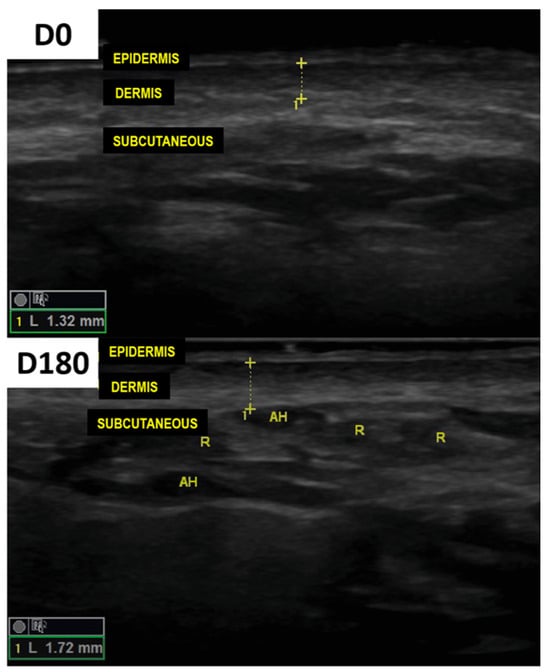

3. Results